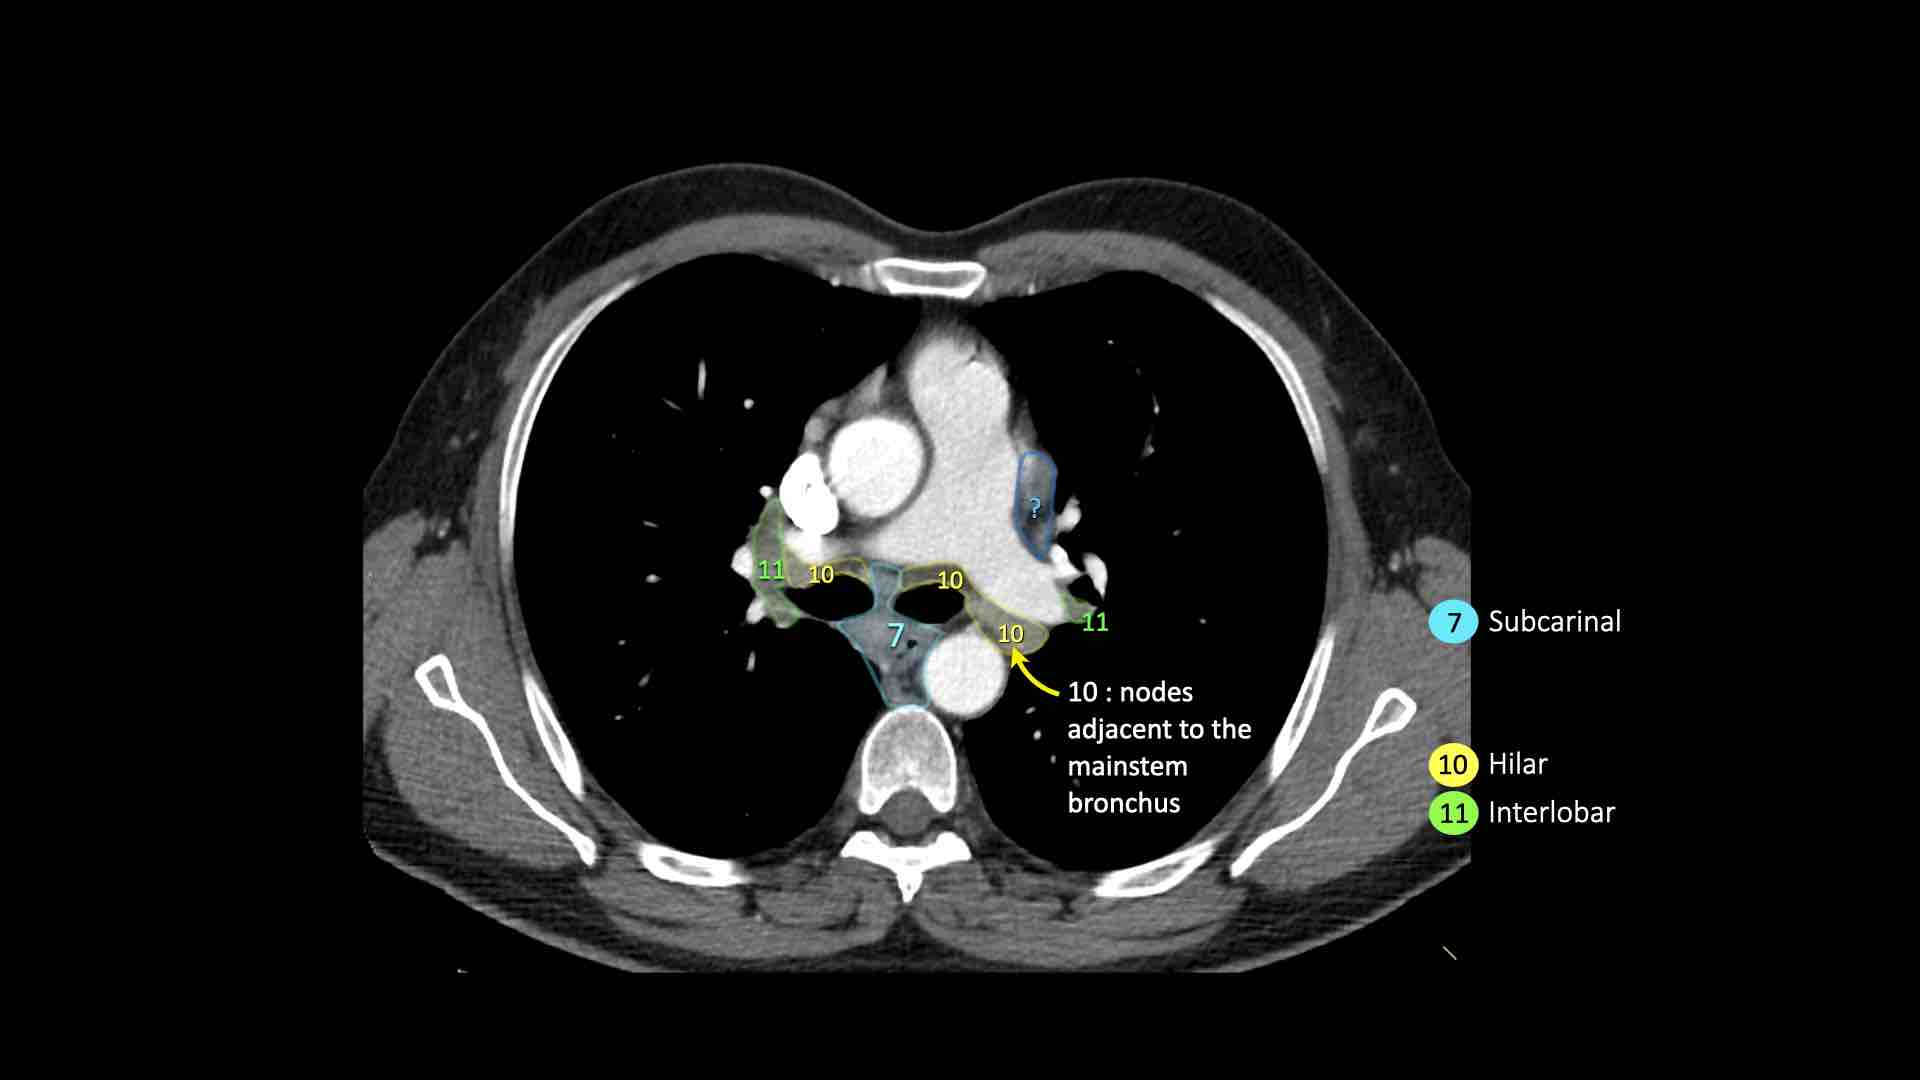

7.Dưới carina

10. Hạch rốn phổi

Bao gồm các hạch tiếp giáp với phế quản gốc và các mạch máu rốn phổi.

7. Hạch dưới carina

Các hạch này nằm ở phía dưới carina khí quản, nhưng không liên quan đến phế quản thùy dưới hoặc các động mạch trong phổi.

Bên phải, chúng trải dài xuống đến bờ dưới phế quản trung gian.

Bên trái, chúng trải dài xuống đến bờ trên phế quản thùy dưới.

Hạch rốn phổi là các hạch thùy gần, nằm ở phía xa so với nếp gấp màng phổi trung thất và các hạch kề phế quản trung gian bên phải.